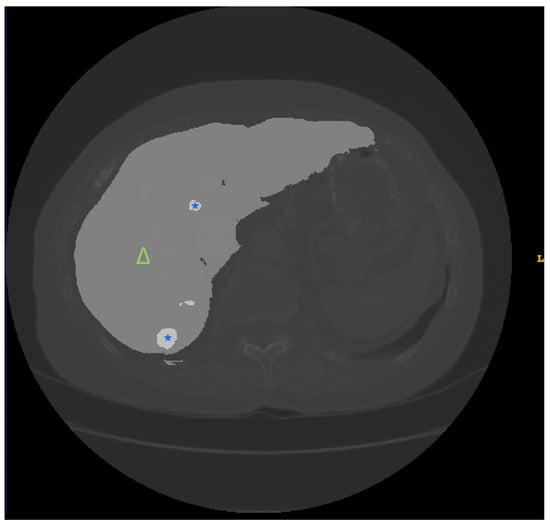

3.1. Public Datasets

- Quinton, F.; Popoff, R.; Presles, B.; Leclerc, S.; Meriaudeau, F.; Nodari, G.; Lopez, O.; Pellegrinelli, J.; Chevallier, O.; Ginhac, D. A Tumour and Liver Automatic Segmentation (ATLAS) Dataset on Contrast-Enhanced Magnetic Resonance Imaging for Hepatocellular Carcinoma. Data 2023, 8, 79. [Google Scholar] [CrossRef]

- Kavur, A.E.; Gezer, N.S.; Barış, M.; Aslan, S.; Conze, P.H.; Groza, V.; Pham, D.D.; Chatterjee, S.; Ernst, P.; Özkan, S.; et al. CHAOS Challenge—combined (CT-MR) healthy abdominal organ segmentation. Med. Image Anal. 2021, 69, 101950. [Google Scholar] [CrossRef] [PubMed]

| ATLAS | Annotated CE-MRI data, particularly for inoperable HCC | First dataset of its kind, suitable for the optimization of contouring in liver cancer treatment planning | Newer datasets requiring validation of compatibility for widespread use |

| CHAOS | Abdominal (kidney, liver, and spleen) CT and MRI scans from 80 patients in DICOM format with ground-truth masks annotated by certified radiologists | Promotes multi-modality imaging research and provides data on healthy organs that are useful for benchmarking | Small sample and lack of pathological information, may be insufficient for model training for pathology detection |